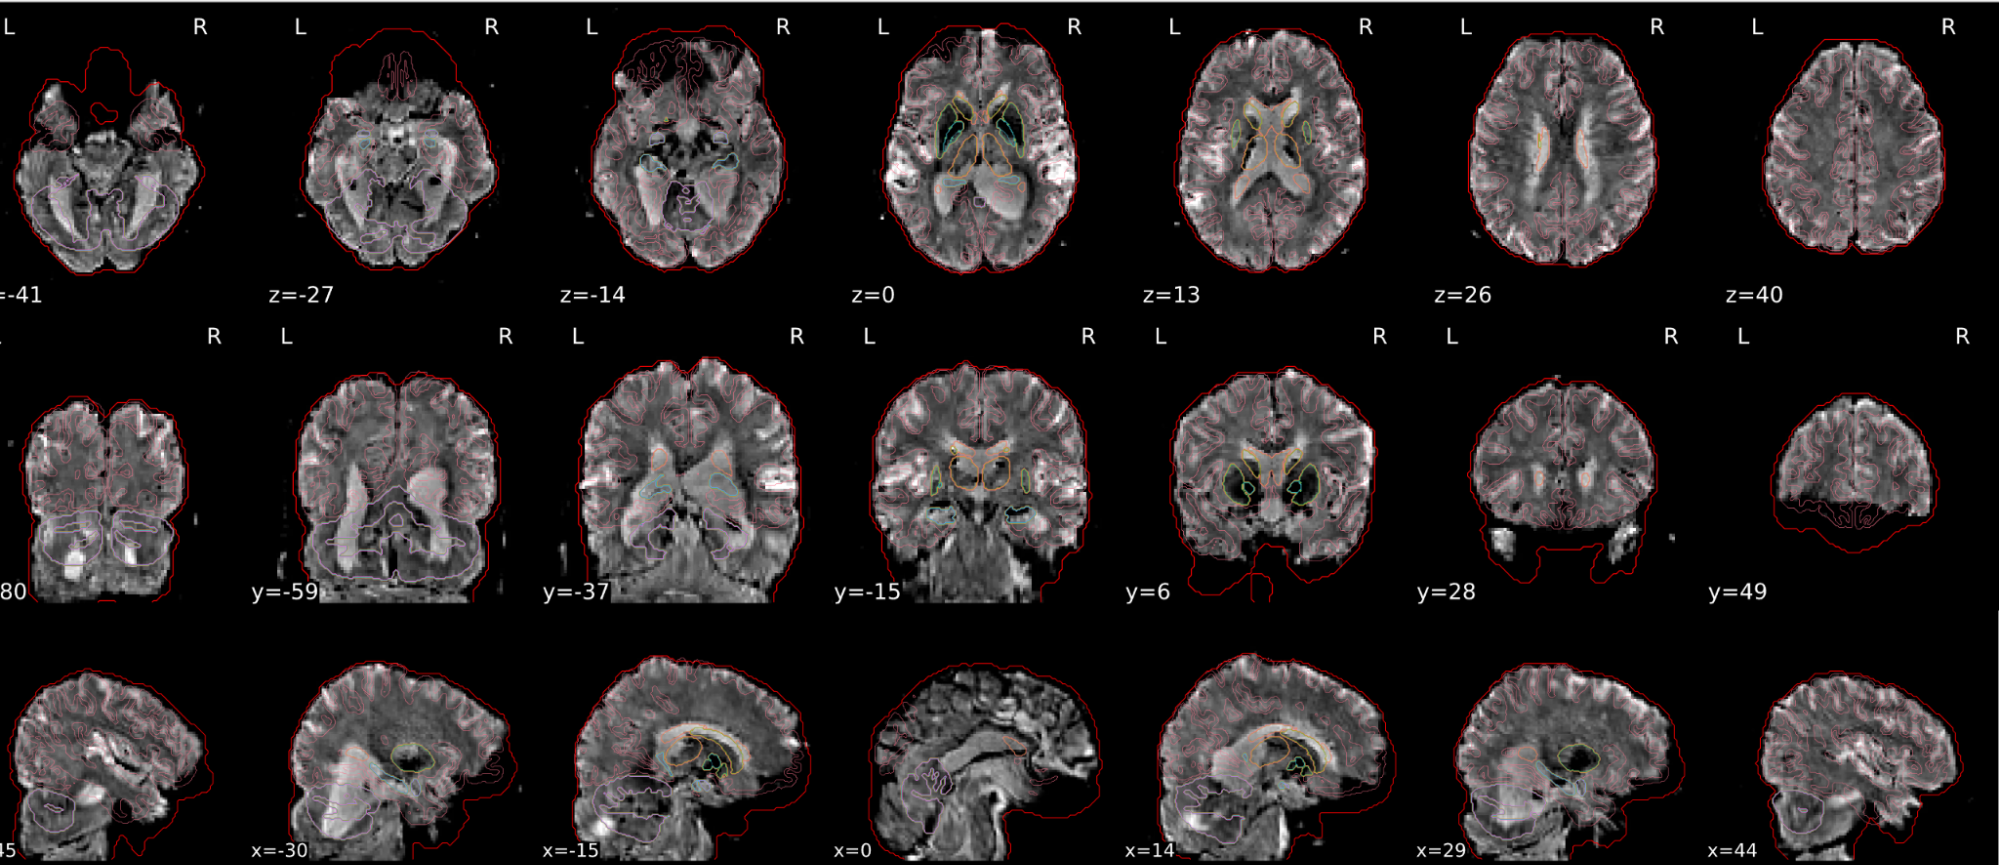

dT1w spatial normalisation

This QC step shows the registration of the T1 image to MNI space.

The registered T1 image is shown in the background with a brain atlas in MNI space as an overlay.

Example of a good subject

- If the registration performed well, you should see an overlap (i.e., correspondence of structures) between the MNI template and the T1 registered to the MNI space.

Example of a bad subject

- In case of poor registration, you should see a misalignment between the MNI template and the T1 (e.g., brain shifted down).

Summary

| good | bad |

|---|---|

| Structures of the MNI template and the registered T1 are well aligned | Structures of the MNI template and the registered T1 aren’t well aligned, e.g. brain is shifted downwards |